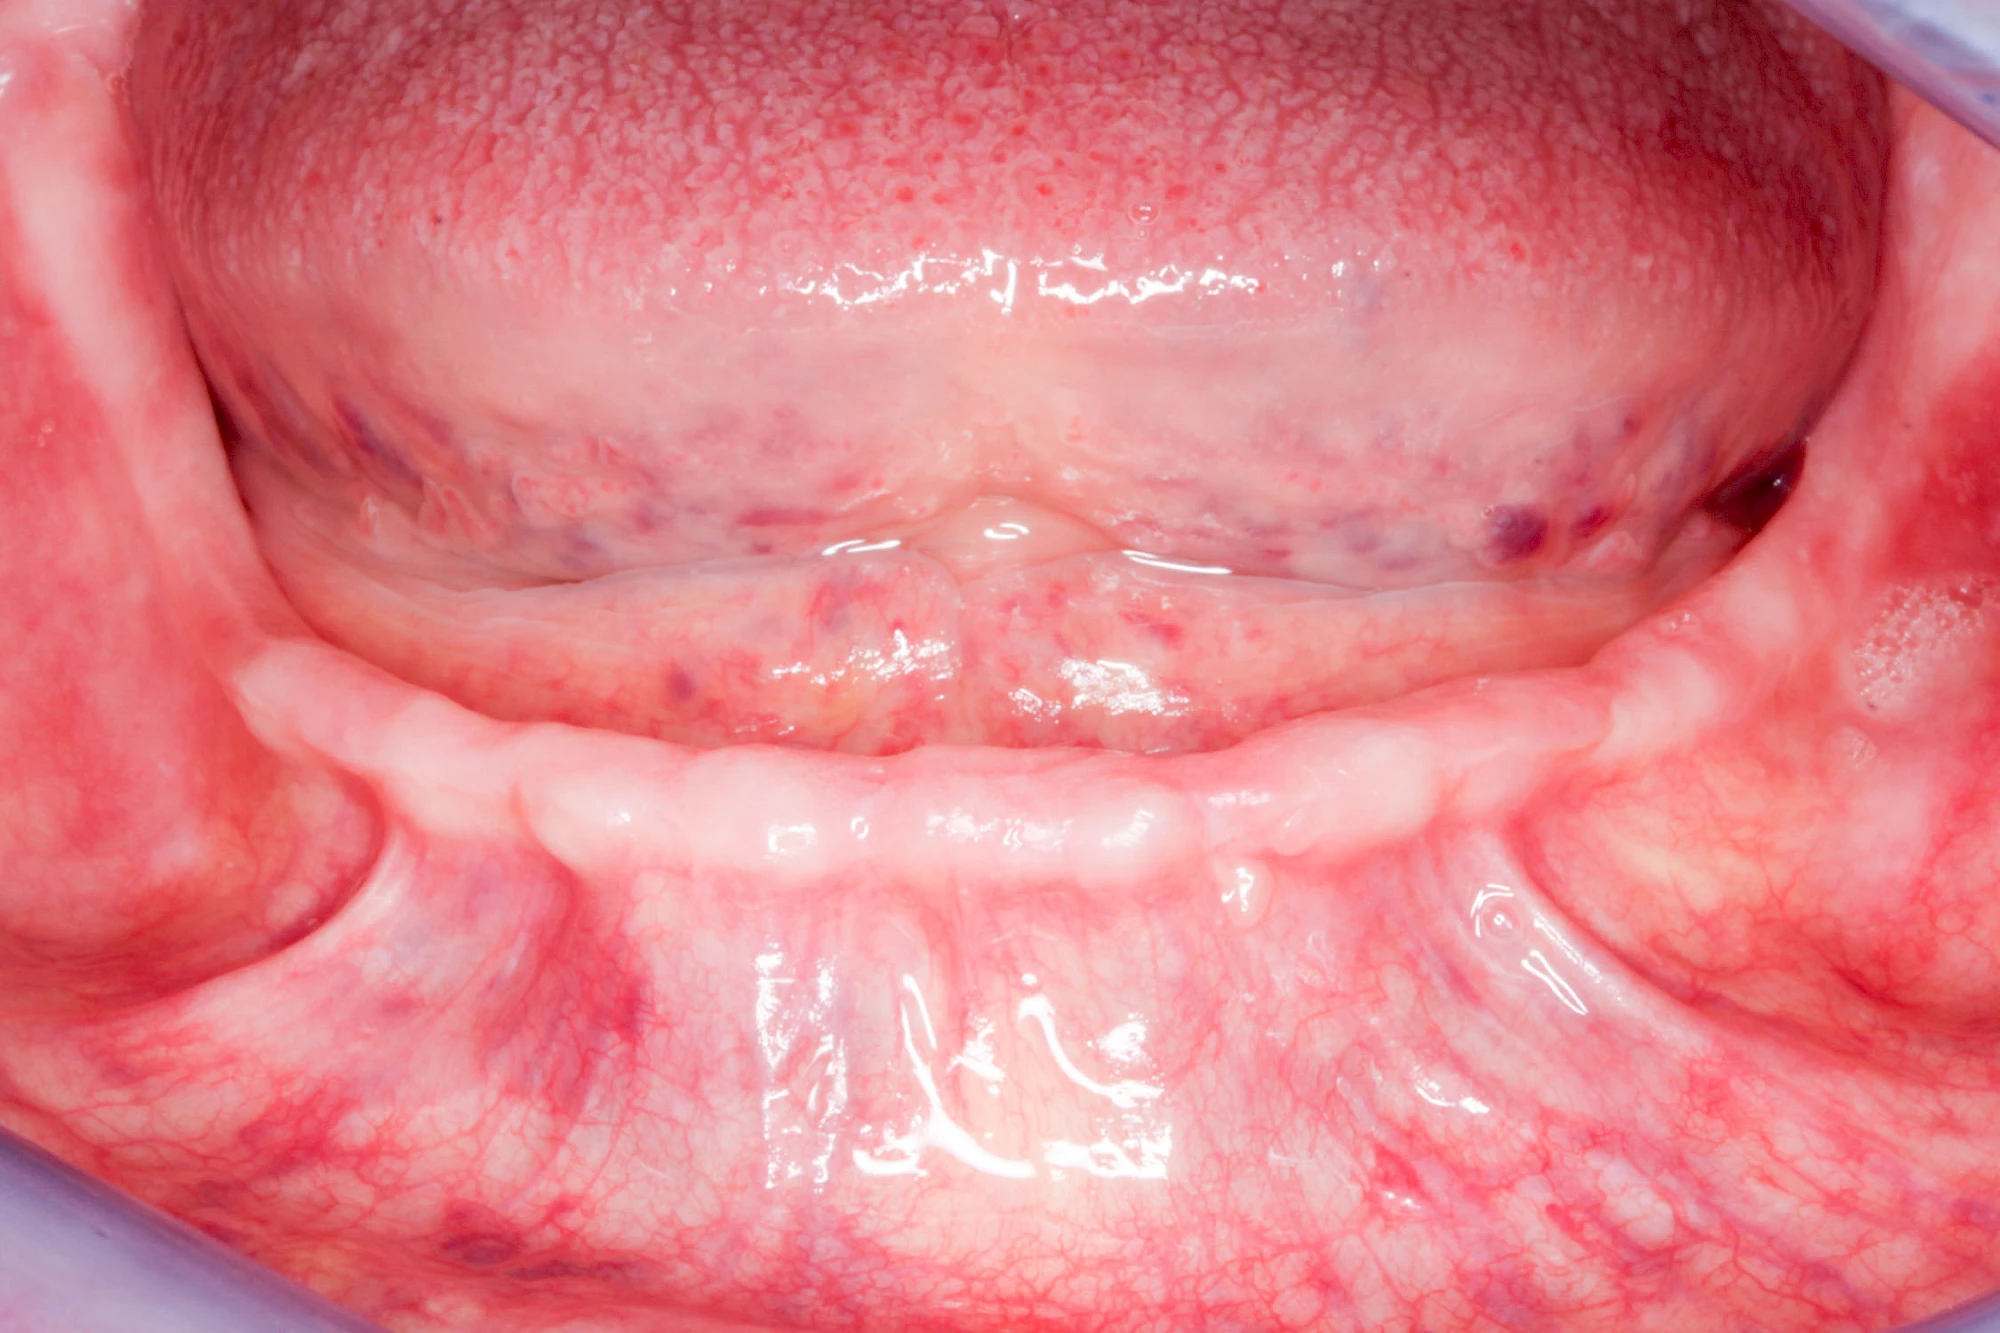

In seltenen Fällen schwindet nur der Knochen, aber nicht die bedeckenden Schleimhäute. In diesen Fällen spricht man von einem sogenannten "Schlotterkamm".